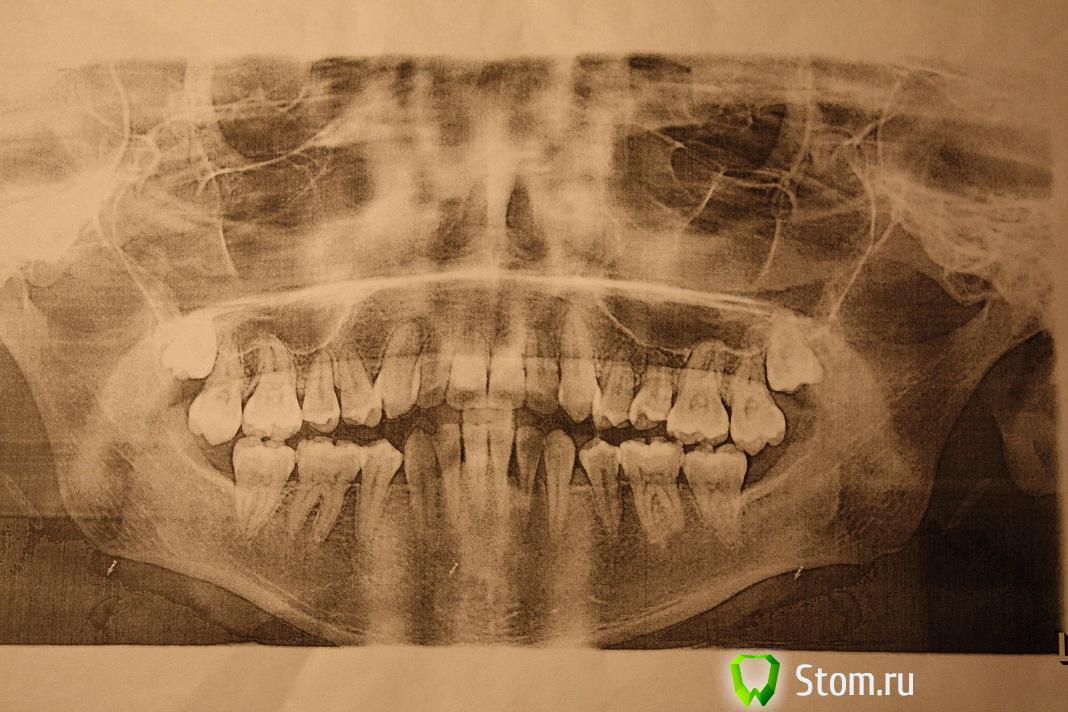

в 11 лет нам пришлось обратиться к ортодонту.причина 1-прямой прикус,2-на верху отсутствуют клыки.Лечение одели пластины и ждали выхода клыков.В это время происходит смена молочных на постоянные зубы,но клыки не выходят.врач отменяет пластинки.одевает брекеты.Удаляет два зуба -четверки нижняя челюсть.на верхней открывает клыки и брекетами ставит на место.Исправление прикуса продолжалось до 16 лет.В 16 положительный результат был достигнут в полной мере.Прикус правильный,клыки на месте,зубы ровные.сняли брекеты и мы пошли домой.В 18 лет опять пришлось обращаться к ортодонту.на верху зубы стали в разные стороны поворачиваться.врач сказала ,что она сделала все что смогла.А повторно одевать брекеты нельзя.мы поняли что лечение закончилось. В 21 год у дочери произошло опущение -десны/фото/

Проходит пол-года,винт раздвинул зубы по максимуму,в результате зубы приняли правильное положение,,а опущенная десна не восстановилась,и добавилась еще одна проблема-нет смыкания зубов вообще.Смыкаются только 6 7 верха с 6 низа с одной стороны.Снимки прилагаются,.Что делать,доктор?